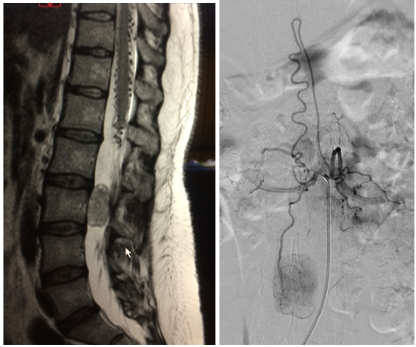

Prueba de elección para tumores de columna y médula espinal. Evalúa partes blandas, relación con la médula y raíces, y detecta compresión, edema, necrosis o hemorragia intratumoral.

Indicado cuando se sospecha metástasis vertebral, para localizar el tumor primario.